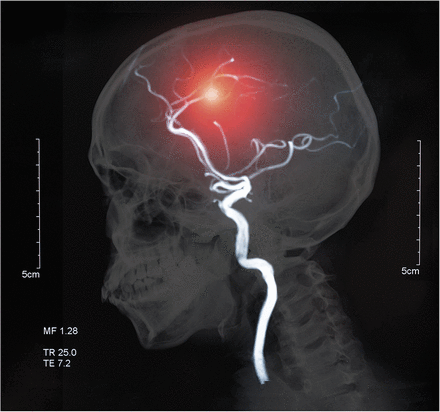

为什么这是一个重要的问题吗?为了更好地理解,我们需要首先考虑动脉瘤和为什么他们可以很严重。动脉瘤的风险是,扩大,这可能(或破裂破裂),这可能会导致因脑出血中风。众所周知,一个人经历破裂动脉瘤是死亡风险高的从这样一个事件(30%)。此外,长期的神经疾病的风险高的人破裂动脉瘤。之前有研究表明,一个人有两个或多个一级亲属(罗斯福)经历了破裂动脉瘤有11%的机会在动脉瘤本身。对这些人来说,一生有20%的机会,动脉瘤破裂。如果一个人有一位罗斯福有动脉瘤破裂,他们应该检查以确定他们是否有现有的未破裂动脉瘤然后监控的发展随着时间的推移,动脉瘤。然而,如果一个人是没有发现动脉瘤破裂?他们的亲属也应该动脉瘤筛查?

本研究是在荷兰进行的2017年4月至2021年10月在乌得勒支大学医学中心,莱顿大学医学中心,阿姆斯特丹大学医学中心。核磁共振血管成像(MRA)先生广泛可用的、非侵入性医疗测试在荷兰。作为这项研究的一部分,犯罪等人发现年龄在20到70年的252人有颅内动脉瘤出现在他们的MRI和MRA。MRI和MRA进行79%的罗斯福这组252人。总的来说,MRI / MRA表现在461年罗斯福的颅内动脉瘤患者(587罗斯福)。一些罗斯福选择不参与,说他们“不想知道”或是“太耗时的[参与]。”1

461年罗斯福的人测试,犯罪等人发现23(或5%)未破裂颅内动脉瘤。他们测量了这些动脉瘤的大小和位置。他们发现,平均而言,动脉瘤是小(3毫米)。他们还计算了5年以后出血的风险,发现低0.7%。22 23人的随访MRI扫描24个月后(1参与者拒绝后续)。在2年以上,有没有变化在动脉瘤的大小或形状。1